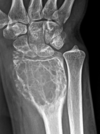

What are the principles of reduction in fracture management?

• Restoring anatomical alignment of fracture or dislocation (see image for why)

• Usually done closed in emergency setting

• Ensure patient has sufficient analgesia (sometimes conscious sedation)

• Three people: one to perform reduction, one to provide counter traction, one to apply plaster